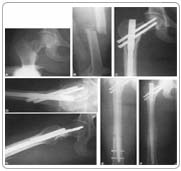

Cheap Femoral Shaft Fracture Internal Fixation Surgery in India

deYou will have a general anaesthetic, and will be asleep for the whole operation. A cut is made in your buttock over the top end of the thigh bone. A steel rod (often called a nail) is then passed down the inside of your thigh bone. It goes across the break and holds your bone in the correct position.

The surgeon may pass some screws across the rod for added stability. The wound is then closed with stitches or clips. There will probably be a fine plastic drainage tube coming out from the wound to drain any residual blood from the operation. You will be in hospital four or five days after the operation.